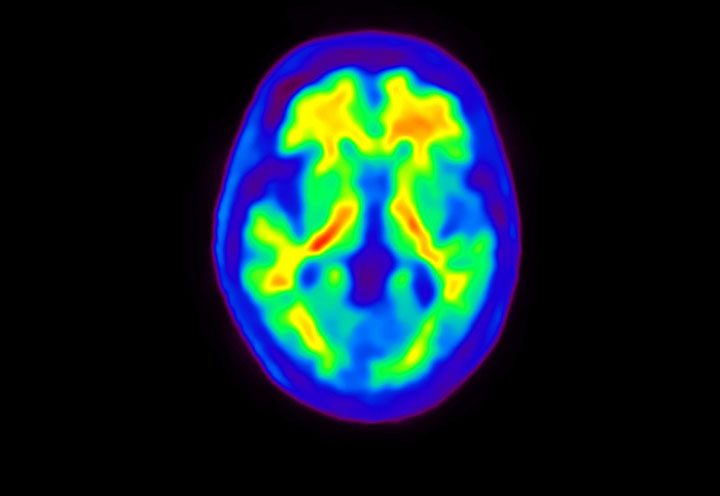

Axial

Courtesy : Kindai University Hospital

- Imaging protocol

- Injected dose: 3.21 MBq/kg, 18F-Flutemetamol

- Uptake time: 100 minutes

- Scan time: 20 minutes